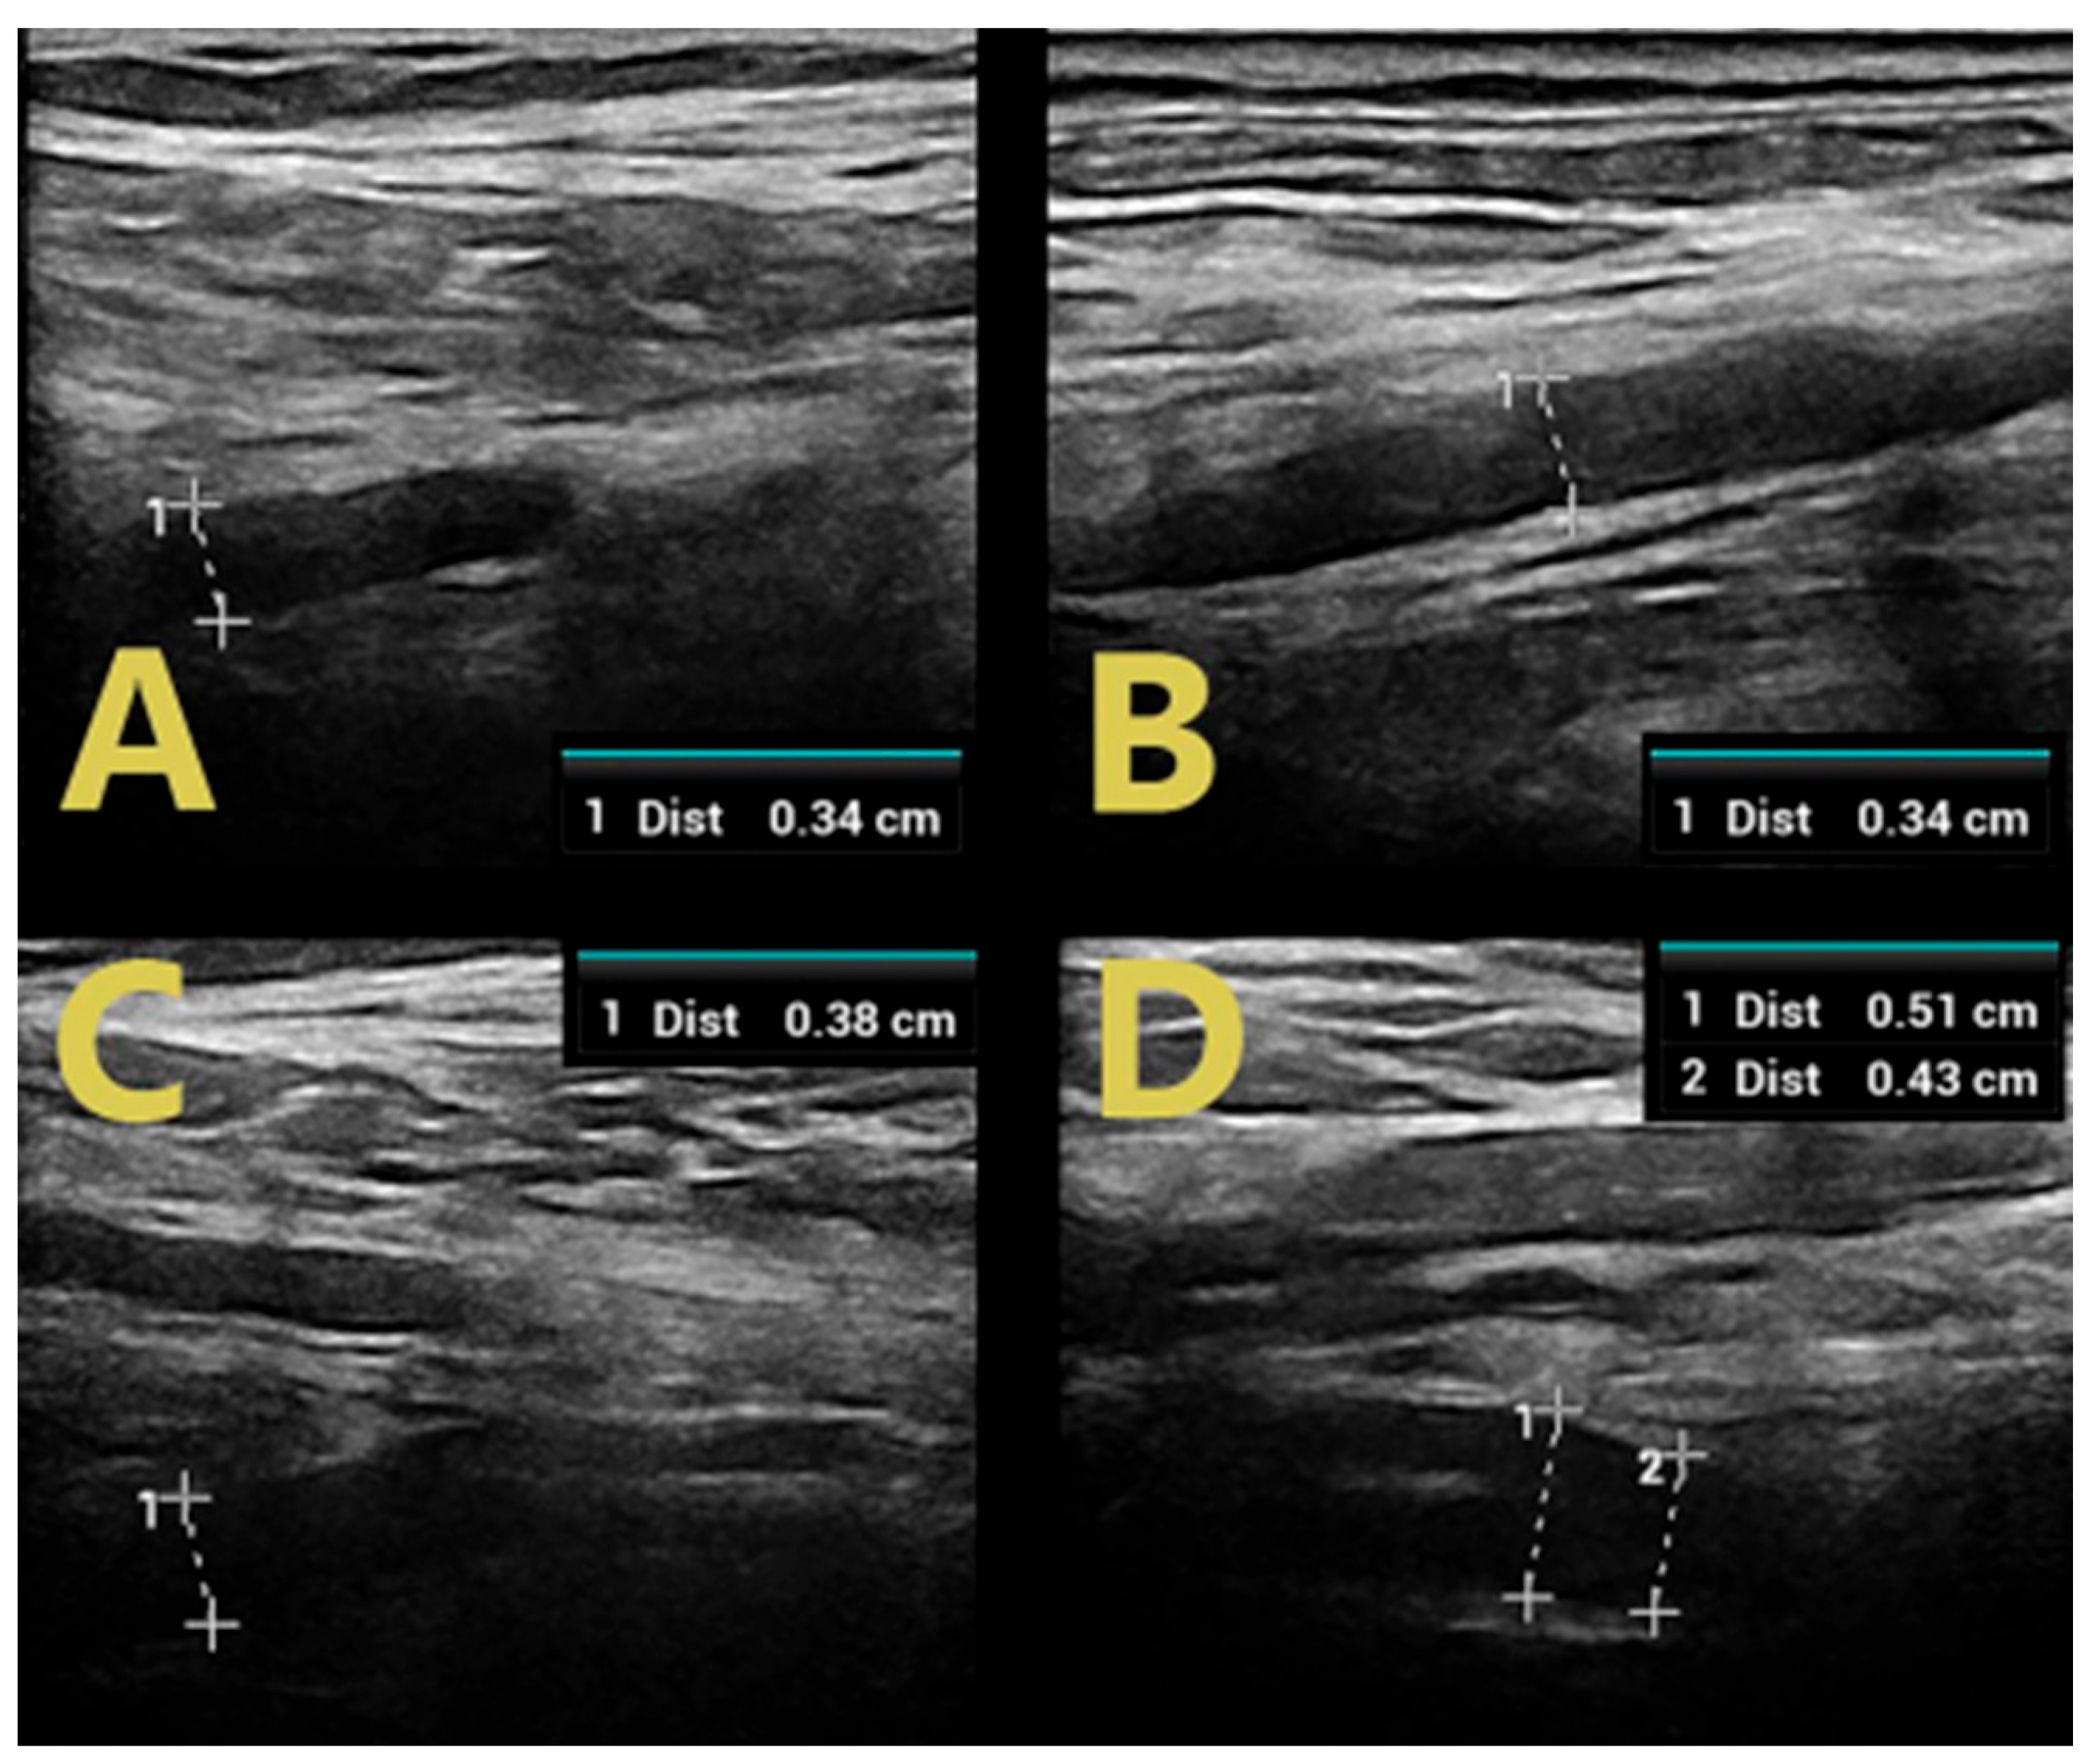

Examination of GBS-confirmed patients revealed mild and regional nerve swelling with mostly hypoechoic bundles (class 1) with a predilection for proximal segments and cervical spinal nerve roots (Figure 2). In the lower limbs, swelling of the tibial and peroneal nerves was visualized only in proximal sections (in the popliteal fossa), with a normal image of the tibial nerve in the tarsal canal (Figure 3).

Figure 2. C5 roots in patients with GBS (A) and CIDP (B), C6 roots in patients with GBS (C), and CIDP (D).